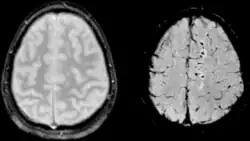

SWI ist ein Magnetresonanztomographie-Verfahren. Sie benutzt flusskompensierte, räumlich hochaufgelöste 3D-Gradientenechosequenzen (GRE-Sequenz) in Einzel- und Multiechotechnik[1] unter Ausnutzung der unterschiedlichen magnetischen Suszeptibilitäten der verschiedenen Gewebe. Diese Unterschiede führen zu einer Phasendifferenz (phase) und bewirken einen Signalverlust (magnitude). Es kommt kein Kontrastmittel zum Einsatz. Mit der Kombination der Signal- und Phasenbilder wird ein erweitertes Kontrastsignalbild erzeugt, welches venöses Blut, (Hirn-)Blutungen und Eisenablagerungen wie Hämosiderin darstellen kann.

Die Bildgebung von venösem Blut mit SWI wird als Blut-Sauerstoff-abhängige Bildgebung (BOLD, blood-oxygen-level dependent) bezeichnet. Venöses (sauerstoffarmes) Blut ist weniger diamagnetisch als arterielles (sauerstoffreiches) Blut. Das Verfahren wurde deshalb ursprünglich als BOLD bezeichnet jedoch später durch den allgemeineren Begriff suszeptibilitätsgewichtete Bildgebung ersetzt. Der Begriff BOLD-Venographie ist heutzutage manchmal noch in Gebrauch. Aufgrund des BOLD-Effektes lässt sich mit SWI das venöse Gefäßsystem gut darstellen.